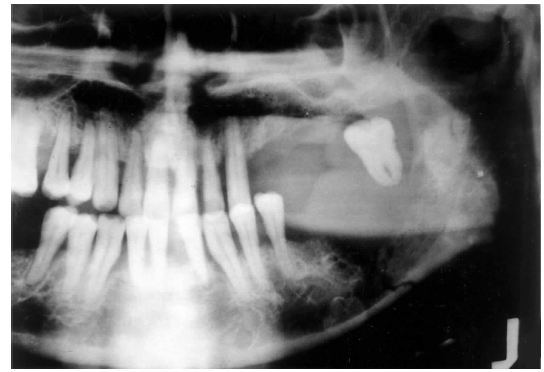

traumatic bone cyst (simple bone cyst)

asymptomatic intra-osseous empty cavity

not a true cyst

may be associated with trauma, patients commonly young

pseudocyst

lined by a thin loose connective tissue, scalloped borders